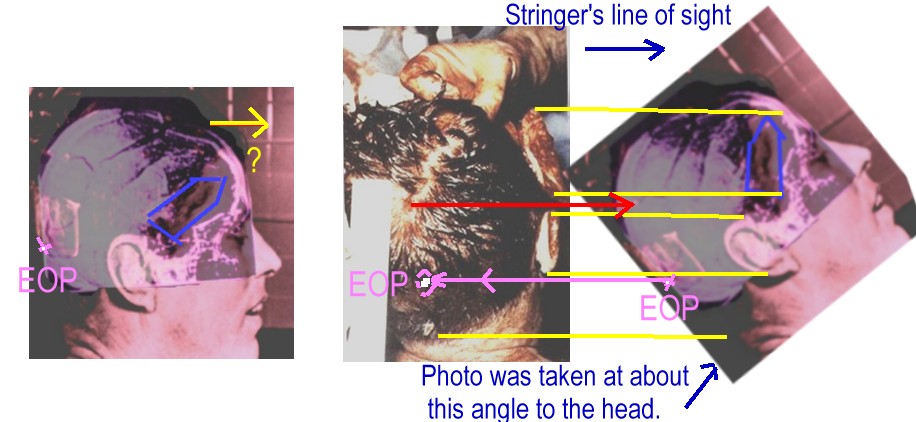

That's what "photo experts" like Robert Groden (in The Killing of a President, page 81) and Harrison Livingstone (in High Treason II) do. Wanting to show the back of Kennedy's head blown out — and thus push the notion of a Grassy Knoll shooter — they use a close-up autopsy photo of the inside of Kennedy's skull after the brain was removed. By rotating the photo ninety degrees clockwise, they can make it appear that the photo shows a large defect in the back of Kennedy's head. In actuality, Kennedy was photographed from the front, and the photo shows the top if his head blasted out, as shown in this drawing by Dr.

Robert Artwohl. Finally, a large and properly-oriented copy of the head photo.

Africanus schrieb:Ich bestreite aber, dass man diese Merkmale aus der Perspektive des Fotos erkennen kann, wenn dieses Foto tatsächlich eine Wunde im Hinterkopf zeigt!

Die Frage ist auch von welchem Aufnahmewinkel du ausgehst. Und da ja auch der parietale Knochen offen war, ergibt sich noch mehr Spielraum.

Und es kommen noch die anderen Faktoren hinzu- lag der Kopf der Seite? Wenn er auf der linken Seite lag wirkte die Schwerkraft auf die stark beschädigte rechte Seite so, dass sie teilweise nach unten/links einsackte? Wird im Gegenszug der Schädel im Gegenzug immer noch festgehalten? etc.

Vergleich mit der Perspektive der Hinterkopffotos